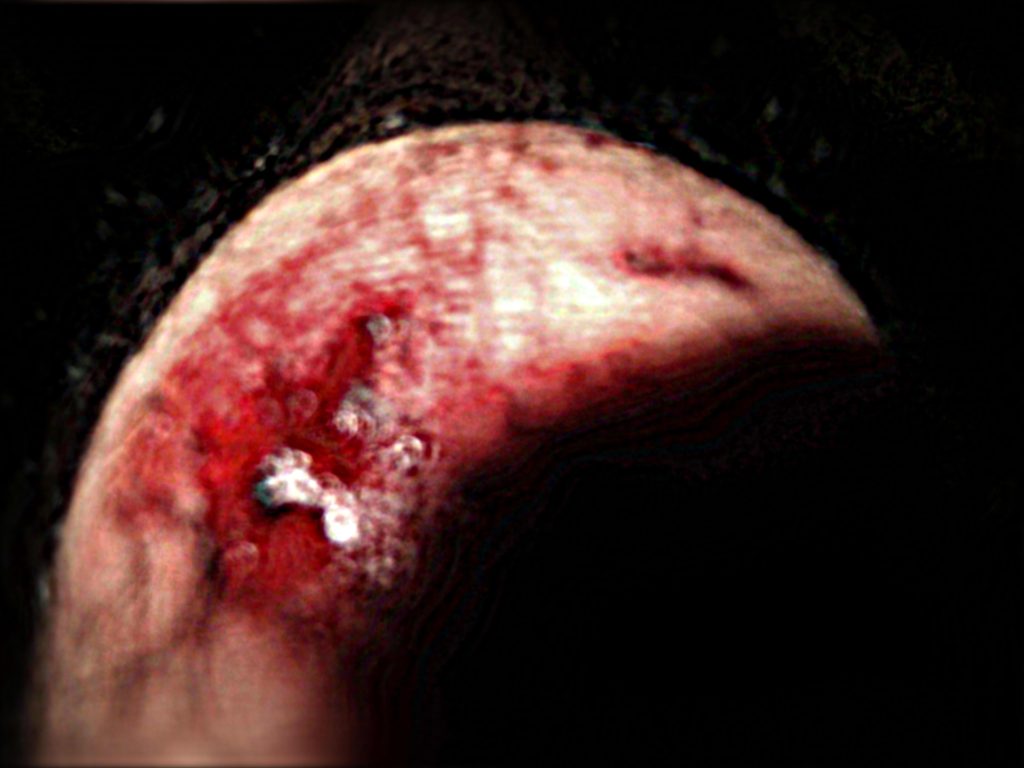

今回は結局は整形外科での精密検査に及ぶレベルの負傷=怪我となりました。

今回のダメージは経験則から観て

自分にとっては割と高度な部類となりました。

X線は10数枚以上に達しました。

現時点では,"顎関節症"と呼ばれる,左耳がくしゃくしゃと話したり食事する度うるさくてしかたがありません!

顎(あご)の左側の関節部が少しずれているのではと思いますが,

相手の外力によって顎の左側に問題は起きていると判断していますが

なんとか帰ってきて,負傷した左の膝を観たところ,やはり膝の皿の外皮がかなり損傷し,血に染まっていました。

"皿の骨"が露出しているのではと見当していましたが,外傷は"高度"ではありませんでした。問題は内部でした。

2.3枚目は顎の怪我で2日目と翌日の3日目(化膿してきたかな)といった画像です。自分が観ても本当に"気持ち悪い画像"ですので,クリックして,あまり観ない方が宜しいかと思います。